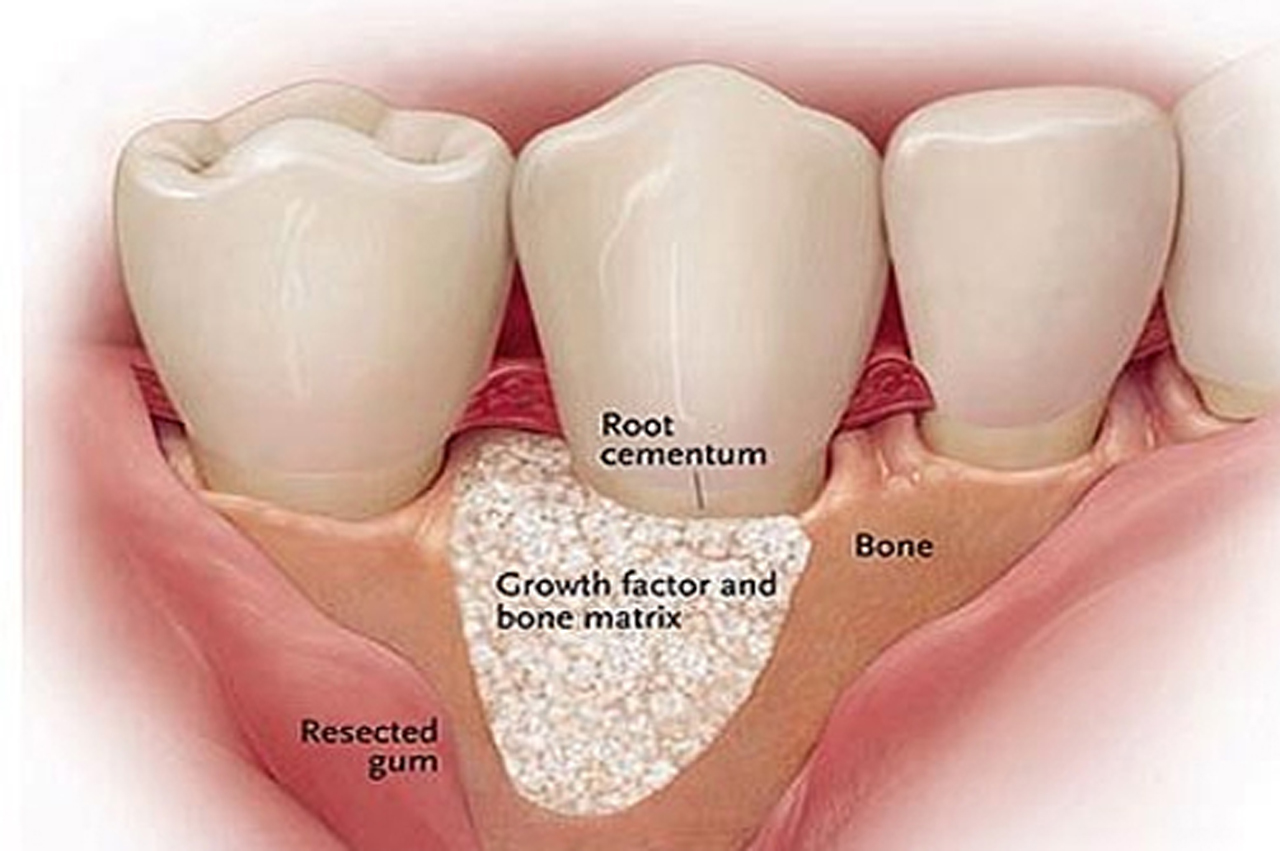

ALL TYPE OF PERIODONTAL SURGERIES